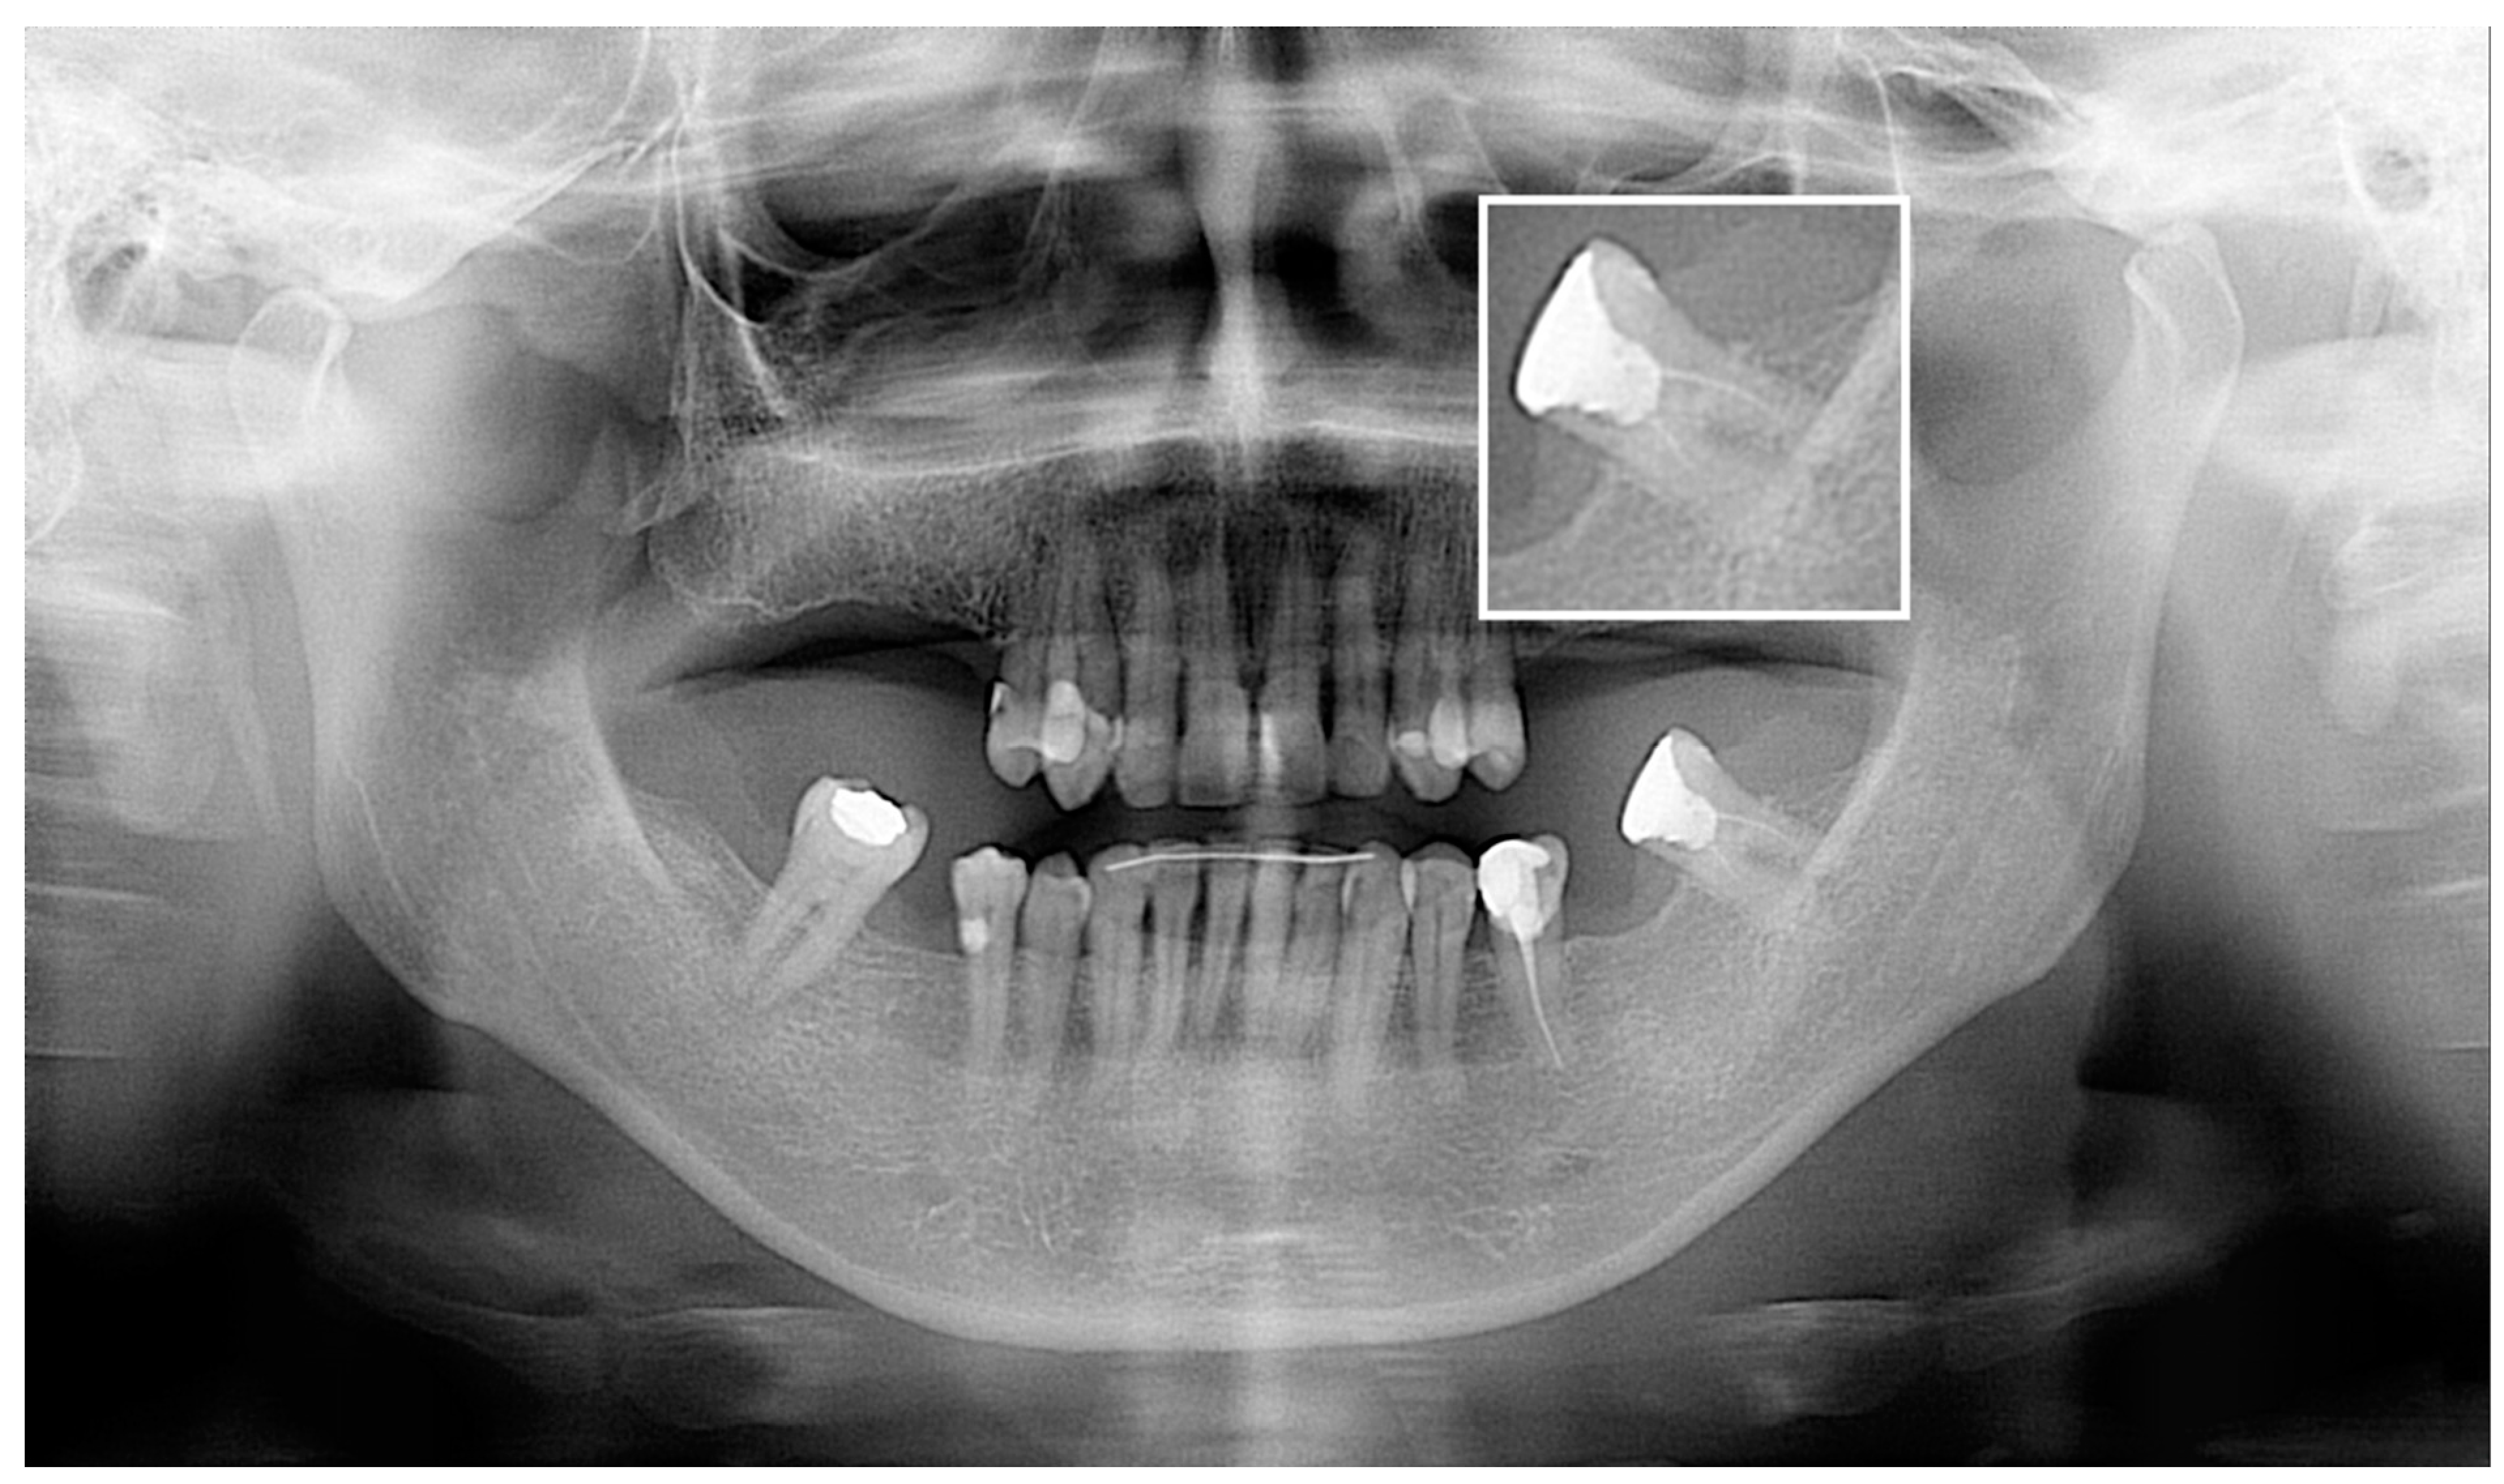

3. Results

3.2. Diagnostic Accuracy Parameters

4. Discussion